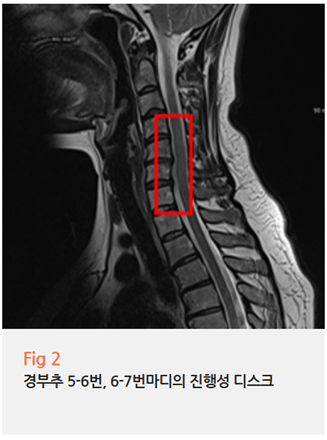

3.0T MRI 검사와 진료를 통해 알아낸 진짜 원인은

바로 목디스크 협착증이었어요

그림2.png 촬영 일시: 2023.10.25

특히 경추 5-6번, 6-7번 사이의 디스크 문제는

오른쪽 가슴 통증의 숨겨진 주범인 경우가 많습니다

이 환자분도 정확히 이 부위에 문제가 있으셨고